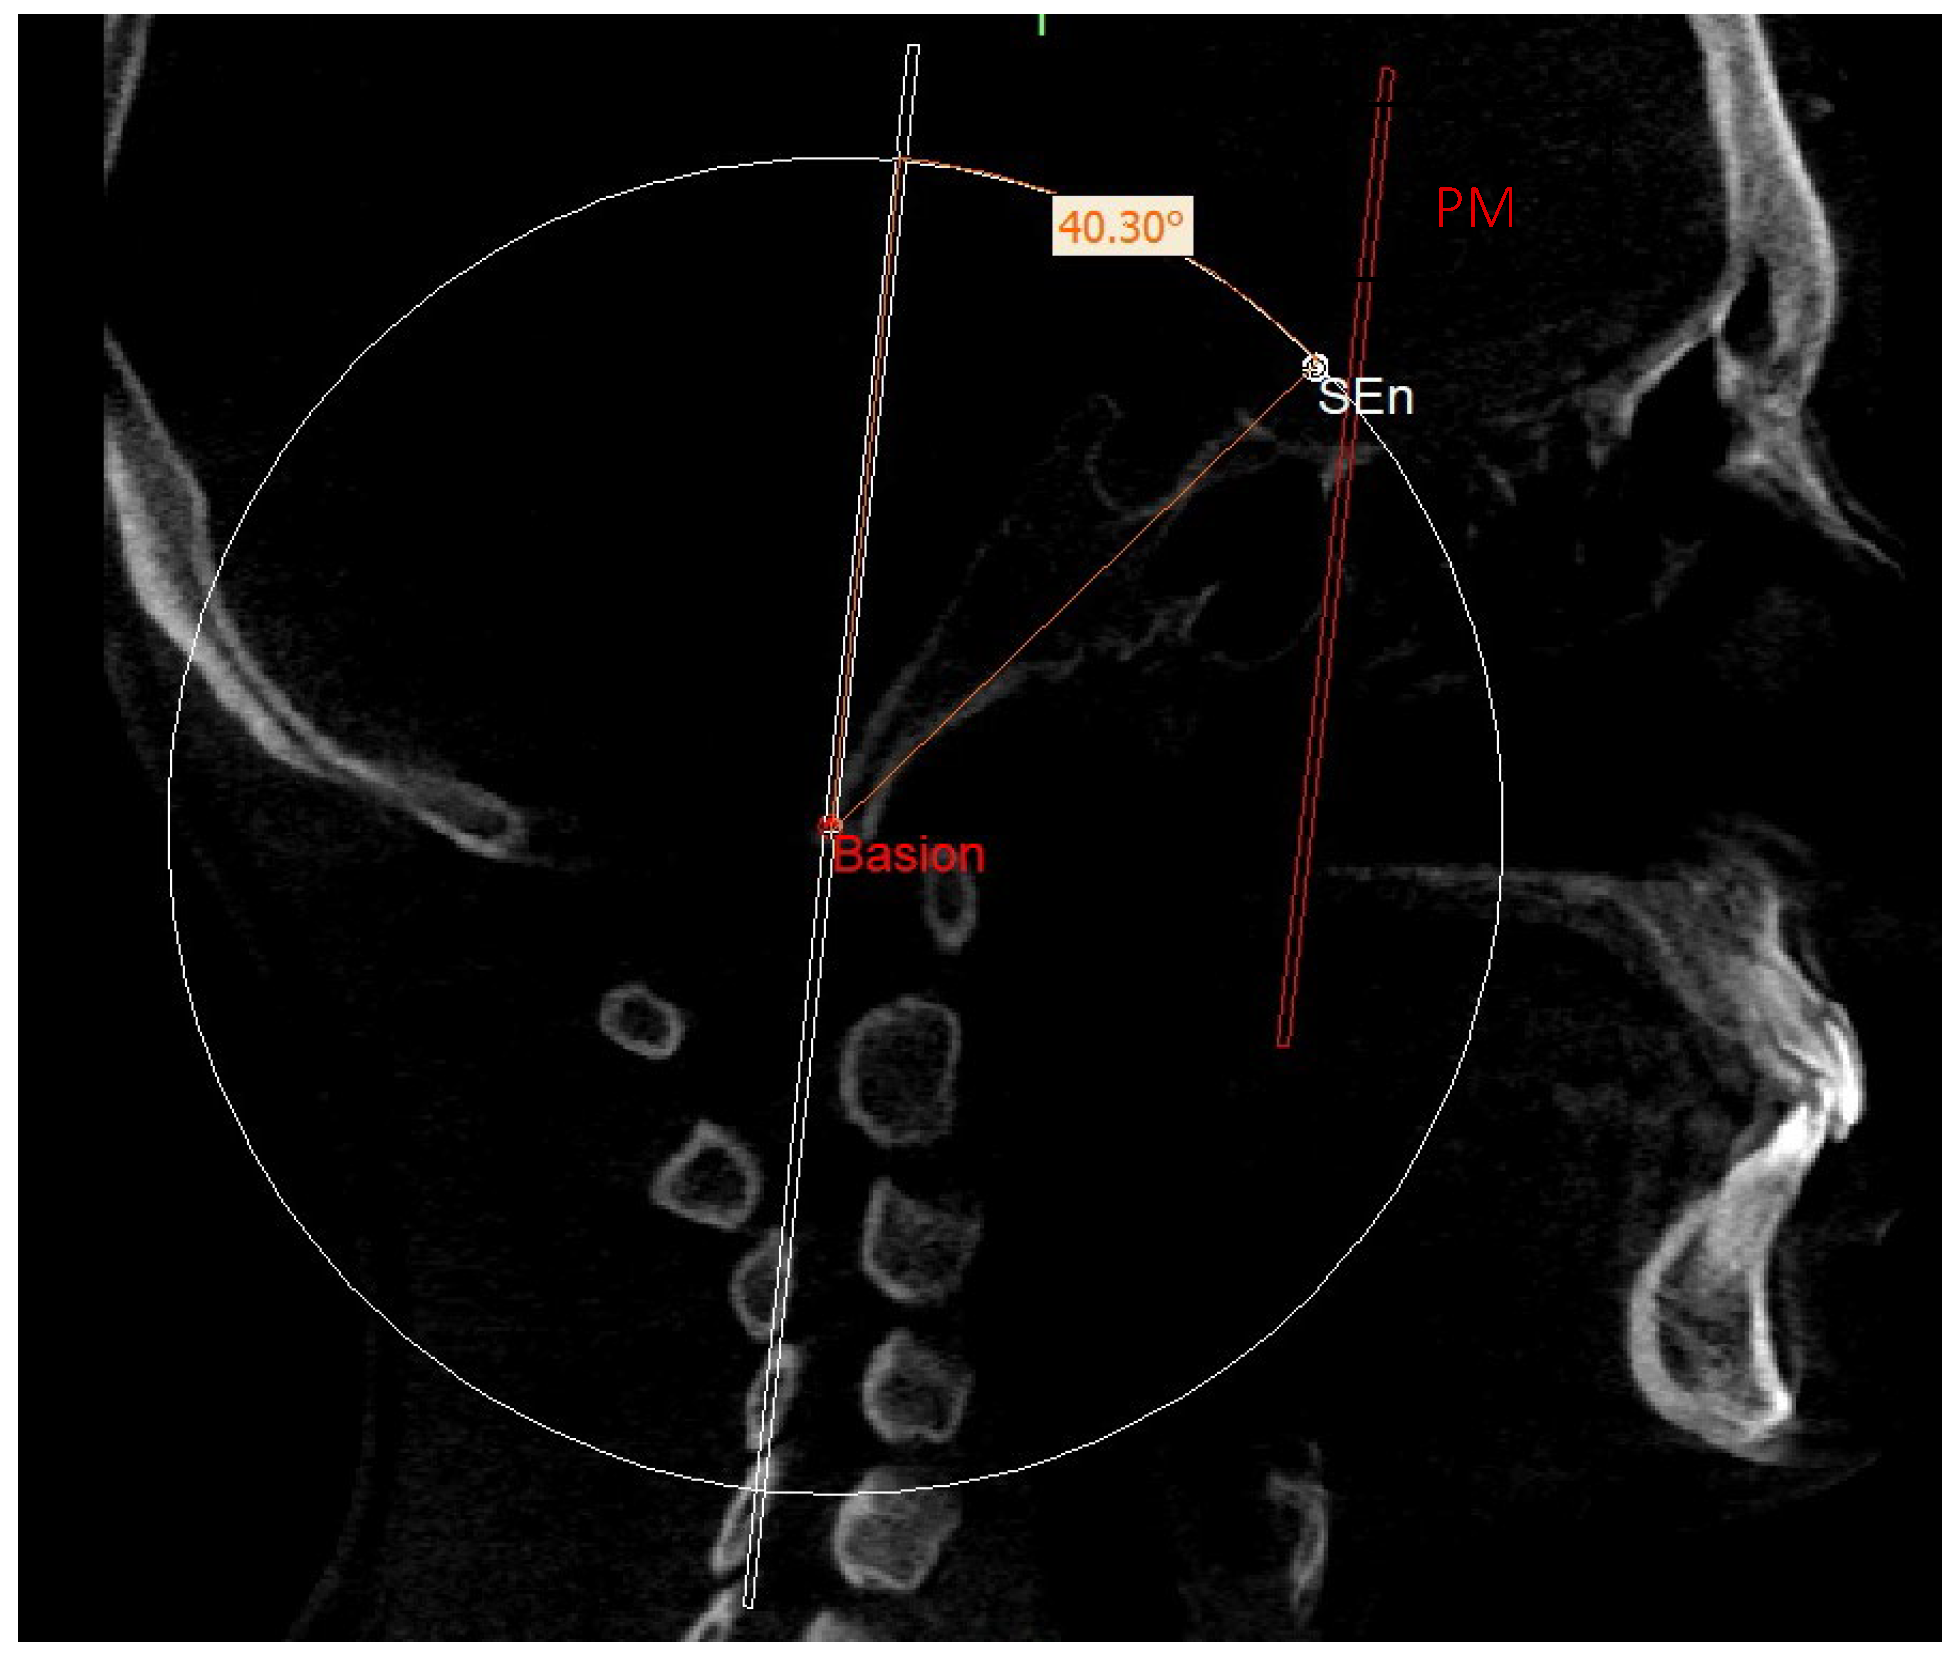

The construction of the neutral track [10] began by drawing a sphere with its center in the Ba point and the radius corresponding to the segment that joins the Ba to the middle point MCF (MCFx) (Figure 8). From this sphere in the sagittal view, we obtained a circumference necessary to identify the neutral sphenoethmoidal junction point (SEn).

In order to localize the SEn point, the geometric construction rule of “parallel lines cut by a transversal line” was used: according to this rule, if two parallel lines are cut by a transversal one, alternate internal angles equal to each other are formed. Therefore, on the sagittal slice where the Ba point is located, we proceeded to trace a plane passing through Ba and parallel to the PM, defined as the construction plane through Ba (CPBa) (Figure 9).

This plan was not directly involved in the definition of the neutral 3D track but was used for the construction of the latter. In fact, an angle of 40.3° was built on this plane so that one side lies on the construction plane and the other side intersects with the circumference. The point of intersection with the circumference identified the SEn (Figure 10).

This point was used to draw the PMn plane which is parallel to the PM plane. In this way, CPBa and PMn represent two parallel lines cut by the BaSEn line and the internal angle that this latter forms with the PMn is 40.3° (Figure 11).

Figure 8. Sphere with radius from Ba to MCFx.

Figure 10. SEn.

Figure 11. PMn plane and SEn point in the sagittal view (a) and on volume rendering (b).